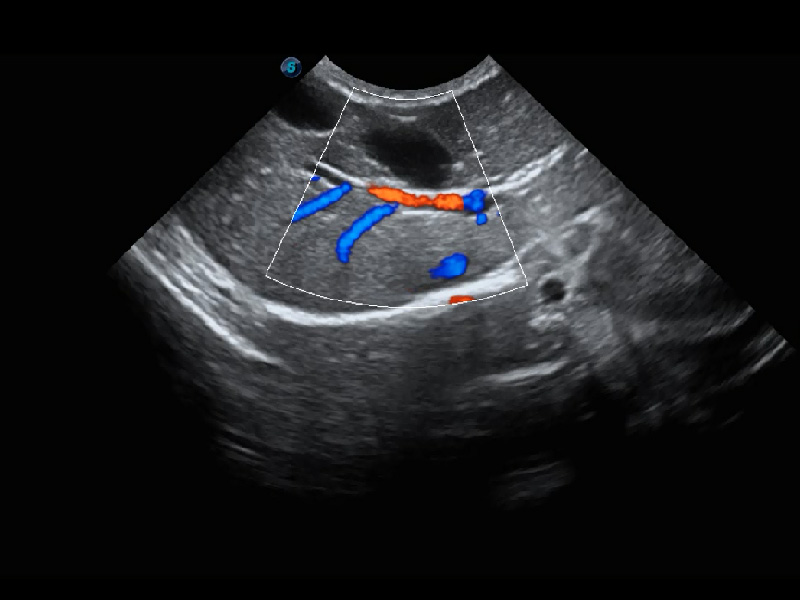

优异的基础图像

(猫)髂动脉血流频谱